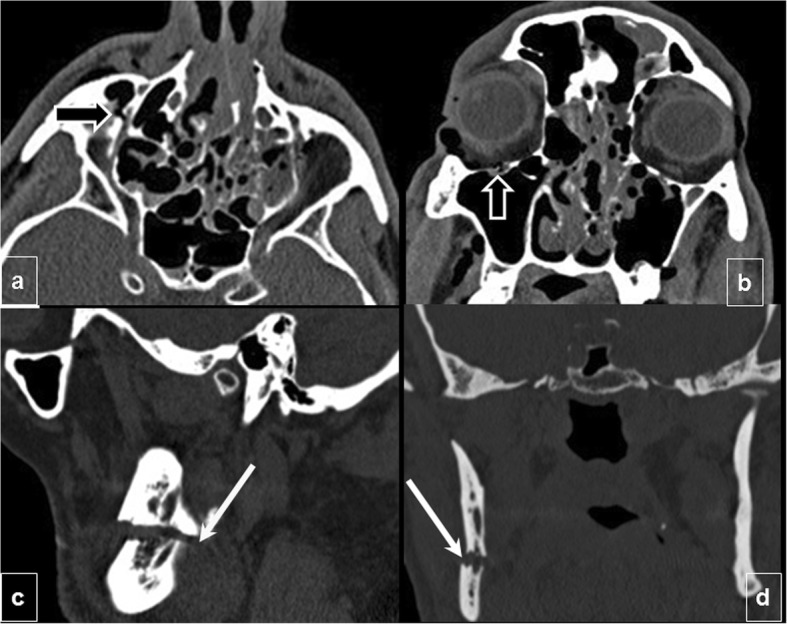

Fig. 3.

Neural foramina complications. Infraorbital canal injury: (a) Axial and (b) coronal CT images show a Le Fort II fracture passing through the infraorbital canal, which can affect the infraorbital nerve (terminal branch of CN V2) (black arrow). c, d Mandibular canal injury: (c) Sagittal and (d) coronal views of a unifocal mandibular fracture passing through the mandibular canal with mild displacement (white arrows) that may damage the inferior alveolar nerve (a branch of CN V3)